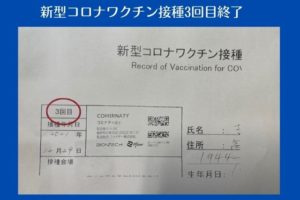

コロナワクチン3回目の接種が終わりました

香川県高松市の噛み合わせ専門歯科医院 吉本歯科医院マネージャー吉本委子です。 吉本歯科医院のスタッフの コロナワクチンの3回目の接種が終わりました。 優しい先生と 優しい看護婦さん 優しい受付の方 […]